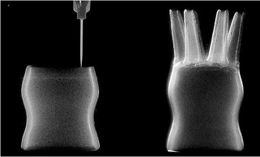

新液體硅膠3D打印工藝是佛羅里達大學的研究人員開發的一種在液體(“油性”微凝膠)中進行的3D打印技術,是繼麻省理工學院(MIT)展示的“凝膠中的3D打印”之后的又一創新!可以改善現有的醫療設備,如植入性帶、柔軟的導管、吊索等等。

漲知識:新液體硅膠3D打印工藝

新液體硅膠3D打印工藝技術通過利用“干擾”的物理過程來實現,其中材料的粘度隨著顆粒密度的增加而增加。3D打印的醫療設備不僅柔軟靈活,而且還可以響應于某些行為而膨脹和收縮,研究人員可以為各種各樣的醫療問題提供解決方案。在此過程中,硅膠被3D打印成微有機凝膠支撐材料。

UF赫伯特·威特海姆學院的機械和航空航天工程博士生Christopher O'Bryan說:“我們的新材料為3D打印提供了液體硅膠的支持,從而使我們能夠制造出非常復雜的結構,甚至由硅橡膠制成的膠囊。

“一旦我們開始將油性硅膠墨水打印到油性微凝膠材料中,打印部件就會保持其形狀,”機械和航空航天副教授湯米•安吉利Tommy Angelini說,“最終的結果是非常好的3D打印硅膠部件,至少是我們見過的最好的。”